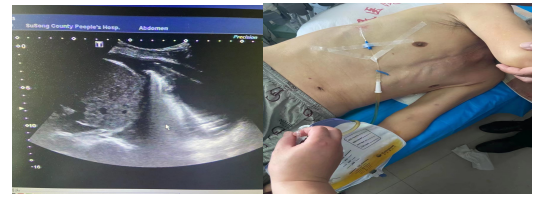

典型病例2 进针间隙窄胸腔积液置管引流

紧贴胸壁实时安全进针 引流成功